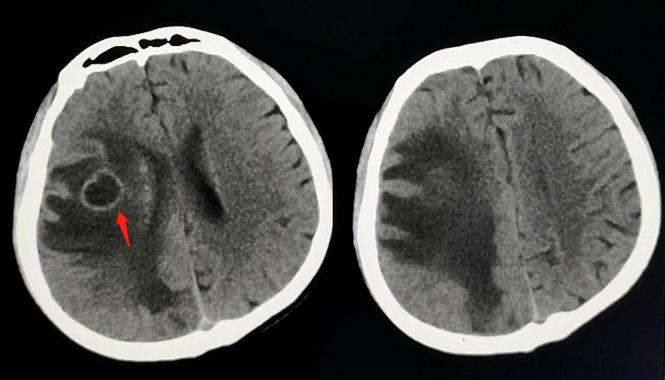

一位22岁的小伙子,走路没力气,无缘无故摔跟头,神经内科医生领着过来做了颅脑CT:

CT显示大脑半球皮质下多发环形病灶,周围大量低密度水肿带,如果是成年人,这个形态要想到转移瘤。

但病人是年轻小伙子,首先考虑脑结核瘤。

这个思路对不对呢?毕竟这些年年轻人长肿瘤的也不少见!

我们对照一下专业书上对脑结核瘤的介绍,看是否吻合:

脑结核瘤( braintuberculoma,BT)是由局限性结核性脑炎演变而成,是结核杆菌在脑实质内形成的慢性肉芽肿;可单发或多发,好发于大脑半球和小脑的皮质下或皮质下区;

可发生于任何年龄段人群,更常见于儿童和青少年;